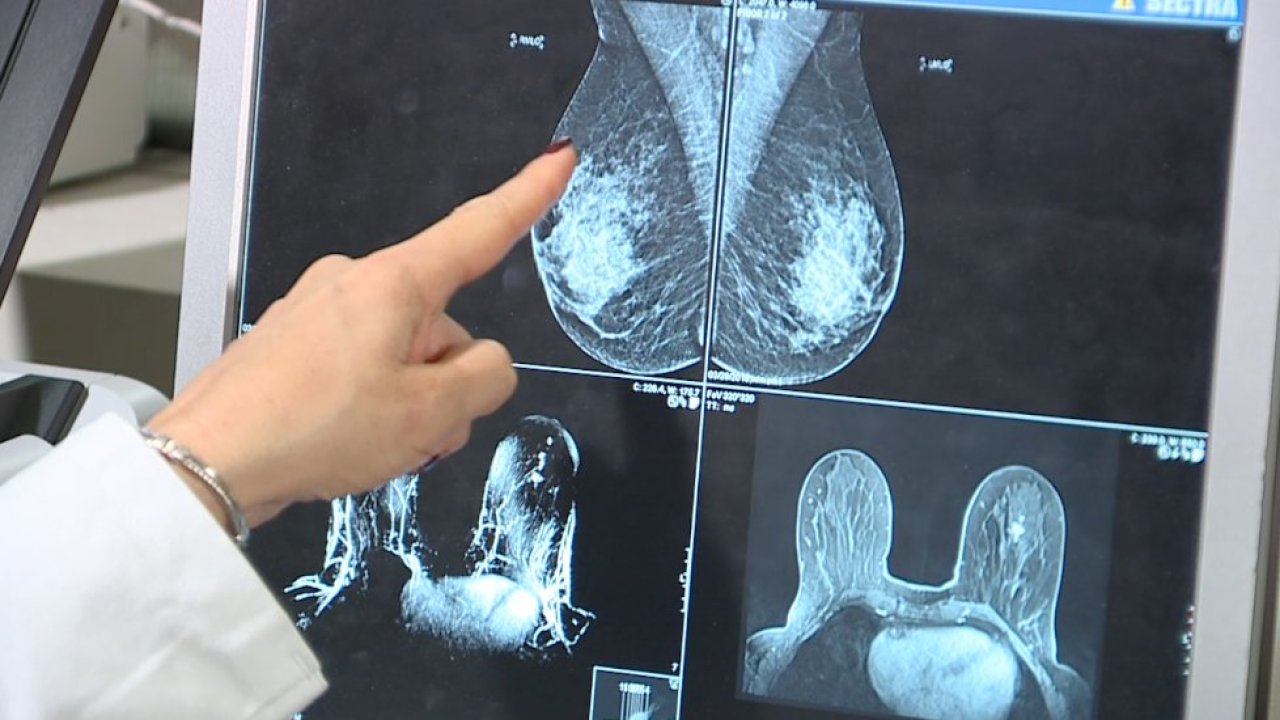

What is Breast MRI?

Breast MRI uses Magnetic Resonance Imaging (MRI) to look at the tissues of the breast. It is a non-invasive study used to further assess if tissue seen by mammography is normal or abnormal. Unlike mammography, Breast MRI does not compress the breast.

It is important to note that Breast MRI is not a replacement for traditional Mammography and breast self-exams but is extremely useful for women who either have a high-risk or a known breast cancer. It is also useful for determining if a woman who has implants has experienced a rupture or if a woman has particularly dense breast tissue.

Each Breast MRI exam produces hundreds of images of the breast, cross-sectional in all three directions (side-to-side, top-to-bottom, front-to-back), which are then read by a Radiologist.